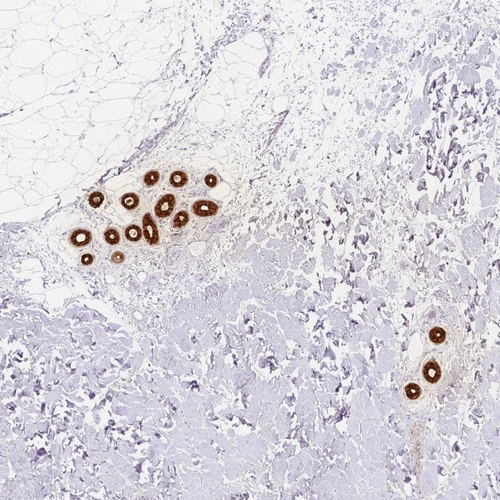

Immunohistochemical staining of human skin shows strong membranous and cytoplasmic positivity in sweat duct cells and secretory cells.